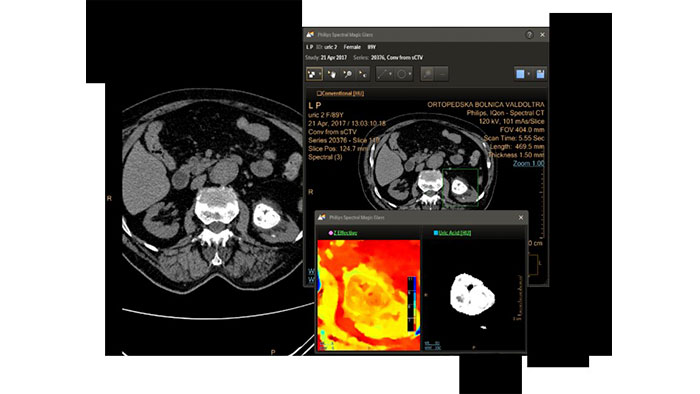

Review spectral data in a range of not spectral-enhanced CT applications

Allows retrospective use of spectral data that was saved in a series of spectral base images (SBI). The fast launch of LMG allows review and identification of the most relevant results to be launched into the application for further analysis.

IQon Spectral CT Functionality

IQon Spectral CT is the only scanner to offer CT Spectral Light Magic Glass and CT Spectral Magic Glass on PACS, helping radiologists review and analyze multiple layers of spectral data at once, including on their PACS.